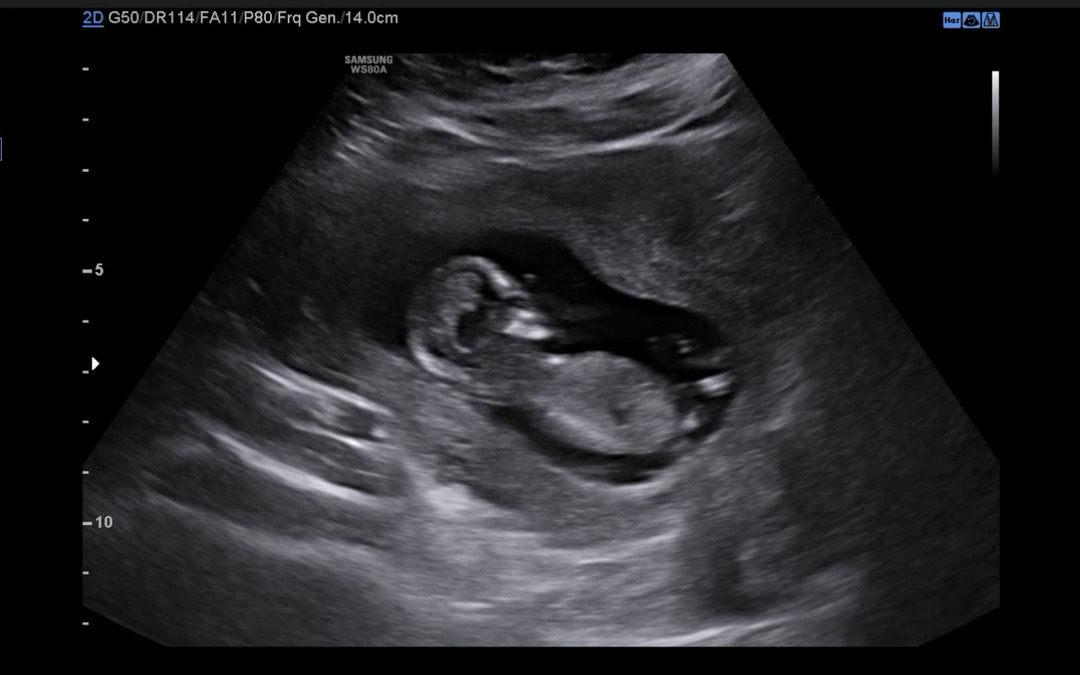

성별 궁금해요 각도법 고수님들 알려주세용

12주3일차입니다 잘보이실까용 ㅠㅠ

각도가 제대로 안나왔어요..ㅠ제글 참고하시고 다른 사진 올려주세요 봐드릴게요 ㅎㅎ

저기 가운데 처럼 자세하게 나와야해요!